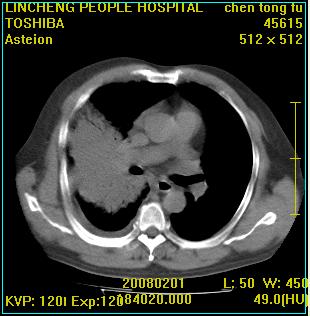

患者,男性,62岁。主因头晕,发热,咳嗽6天,高热达39度,esr19mm/h,wbc 3.9×10 9/l

实变区见空气支气管征,支气管通畅,考虑为大叶性肺炎,右侧少量胸水

1)考虑为:右肺感染性病变。建议:抗炎治疗复查。2)右侧少量胸腔积液。

右肺炎症并右侧胸腔少量积液。